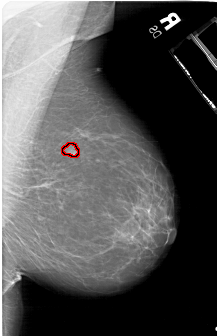

A_1177_1.RIGHT_CC

RIGHT_CC LINES 5881 PIXELS_PER_LINE 4156 BITS_PER_PIXEL 12 RESOLUTION 43.5 OVERLAY

FILE: A_1177_1.RIGHT_CC.OVERLAY

TOTAL_ABNORMALITIES 1

ABNORMALITY 1

LESION_TYPE MASS SHAPE LOBULATED MARGINS OBSCURED

ASSESSMENT 3

SUBTLETY 4

PATHOLOGY BENIGN

TOTAL_OUTLINES 1

BOUNDARY